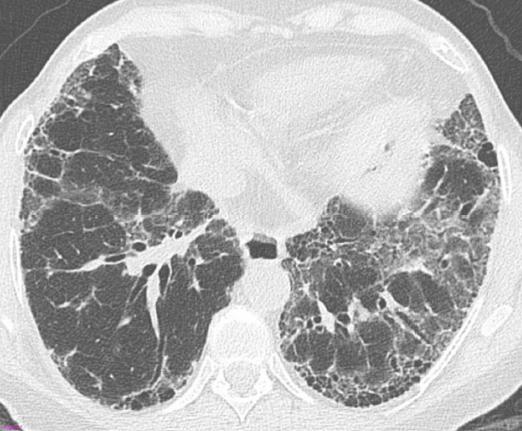

La radiografia del torace (RX) rimane il punto di partenza per la classificazione della sarcoidosi polmonare, utilizzando il sistema di Scadding che divide la malattia in quattro stadi principali sulla base dei reperti linfo-parenchimali.[1, 12, 13]

| IV | Fibrosi polmonare diffusa | Presenza di cicatrici permanenti, perdita di volume e cisti |

Tuttavia, la TC ad alta risoluzione (HRCT) è oggi considerata indispensabile per una migliore caratterizzazione. I segni tipici alla HRCT includono noduli a distribuzione perilinfatica (lungo i setti interlobulari e le scissure), ispessimento dei fasci broncovascolari e opacità a “vetro smerigliato” che riflettono un’alveolite granulomatosa attiva.